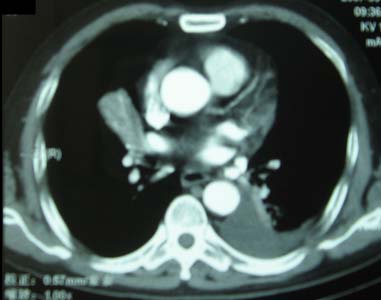

以下是引用zhangzhongshou在2007-5-17 12:08:00的发言:[br]1、右肺中叶不张,建议纤支镜检查。[br]2、左侧胸腔积液,性质待查,建议进一步检查。[br]3、左侧局限性胸膜肥厚。[br][br][本贴已被 zhangzhongshou 于 2007-5-17 12:12:13 修改过]

以下是引用zyx168在2007-5-17 12:44:00的发言:[br]支持[br] 1、右肺中叶不张,建议纤支镜检查。[br] 2、左侧胸腔积液,性质待查,建议进一步检查。[br] 3、左侧局限性胸膜肥厚。 [br]

以下是引用一棵树在2007-5-17 12:11:00的发言:[br]中叶的病变应该谨慎,建议支气管镜检查。